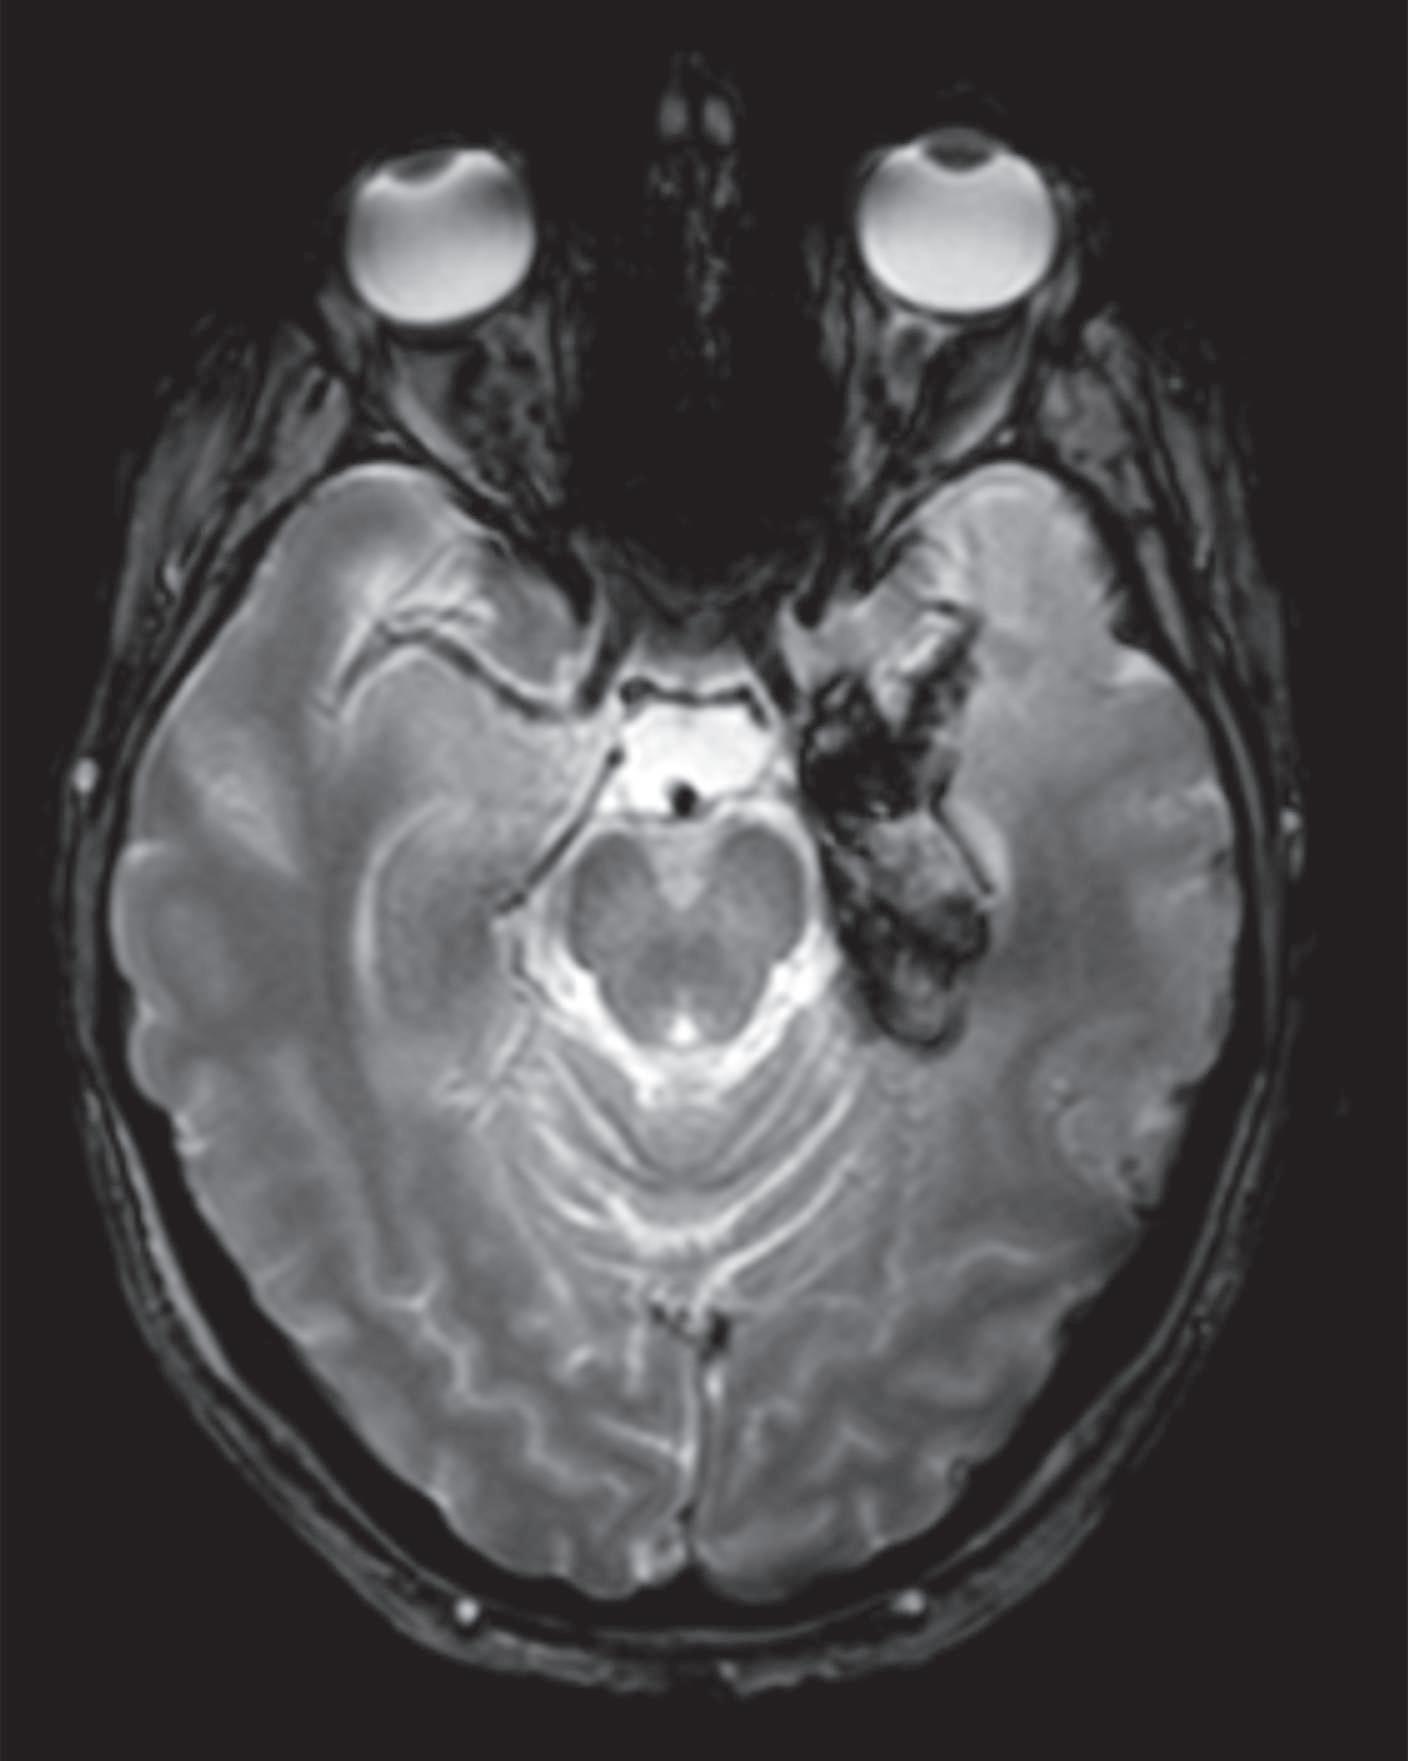

A encefalite herpética é a encefalite esporádica mais comum, associando-se a uma mortalidade e morbilidade importantes na ausência de tratamento atempado. A infeção ocorre primariamente, após exposição a secreções respiratórias ou saliva infetadas, ou por reativação do vírus latente no gânglio do nervo trigémeo. Atinge, predominantemente o lobo temporal mesial e a região orbitofrontal, podendo causar afasia, alterações comportamentais e mnésicas proeminentes. A RM CE caracteriza se por insuflação e hipersinal T2/FLAIR (fluid-attenuated inversion recovery)/DWI (diffusion­weighted imaging), podendo desenvolver áreas de necrose hemorrágica (Figura 12.1). No entanto, em cerca 5% dos casos a RM-CE pode ser normal. O EEG revela geralmente lentificação da atividade de base e descargas periódicas nas regiões temporais uni

ou bilateralmente. O LCR pode ser normal na fase inicial mas, tipicamente, apresenta características de meningite viral, podendo conter eritrócitos e xantocromia pela presença de áreas hemorrágicas no parênquima cerebral. O diagnóstico é confirmado pela pesquisa do vírus no LCR por PCR. Este teste apresenta uma elevada sensibilidade (96%) e especificidade (99%), no entanto falsos negativos podem ocorrer, sobretudo se efetuado precocemente (< 48 horas) e na presença de produtos de degradação de hemoglobina no LCR. Quando a suspeita clínica se mantém, a terapêutica antiviral deve ser mantida, repetindo-se a PL entre os 3º-7º dias de doença.

A B C D E F

Figura 12.1 – Encefalite herpética. RM-CE mostra hipersinal e aspeto insuflativo em FLAIR da região temporomesial e ínsula à esquerda no D3 de doença (A-C); marcado aumento da extensão das lesões no D38 de doença com hipersinal em FLAIR na região temporomesial bilateralmente com maior extensão à esquerda e opérculo-insular (D, E), associado a componente hemorrágico na região temporal interna em T2* (F).